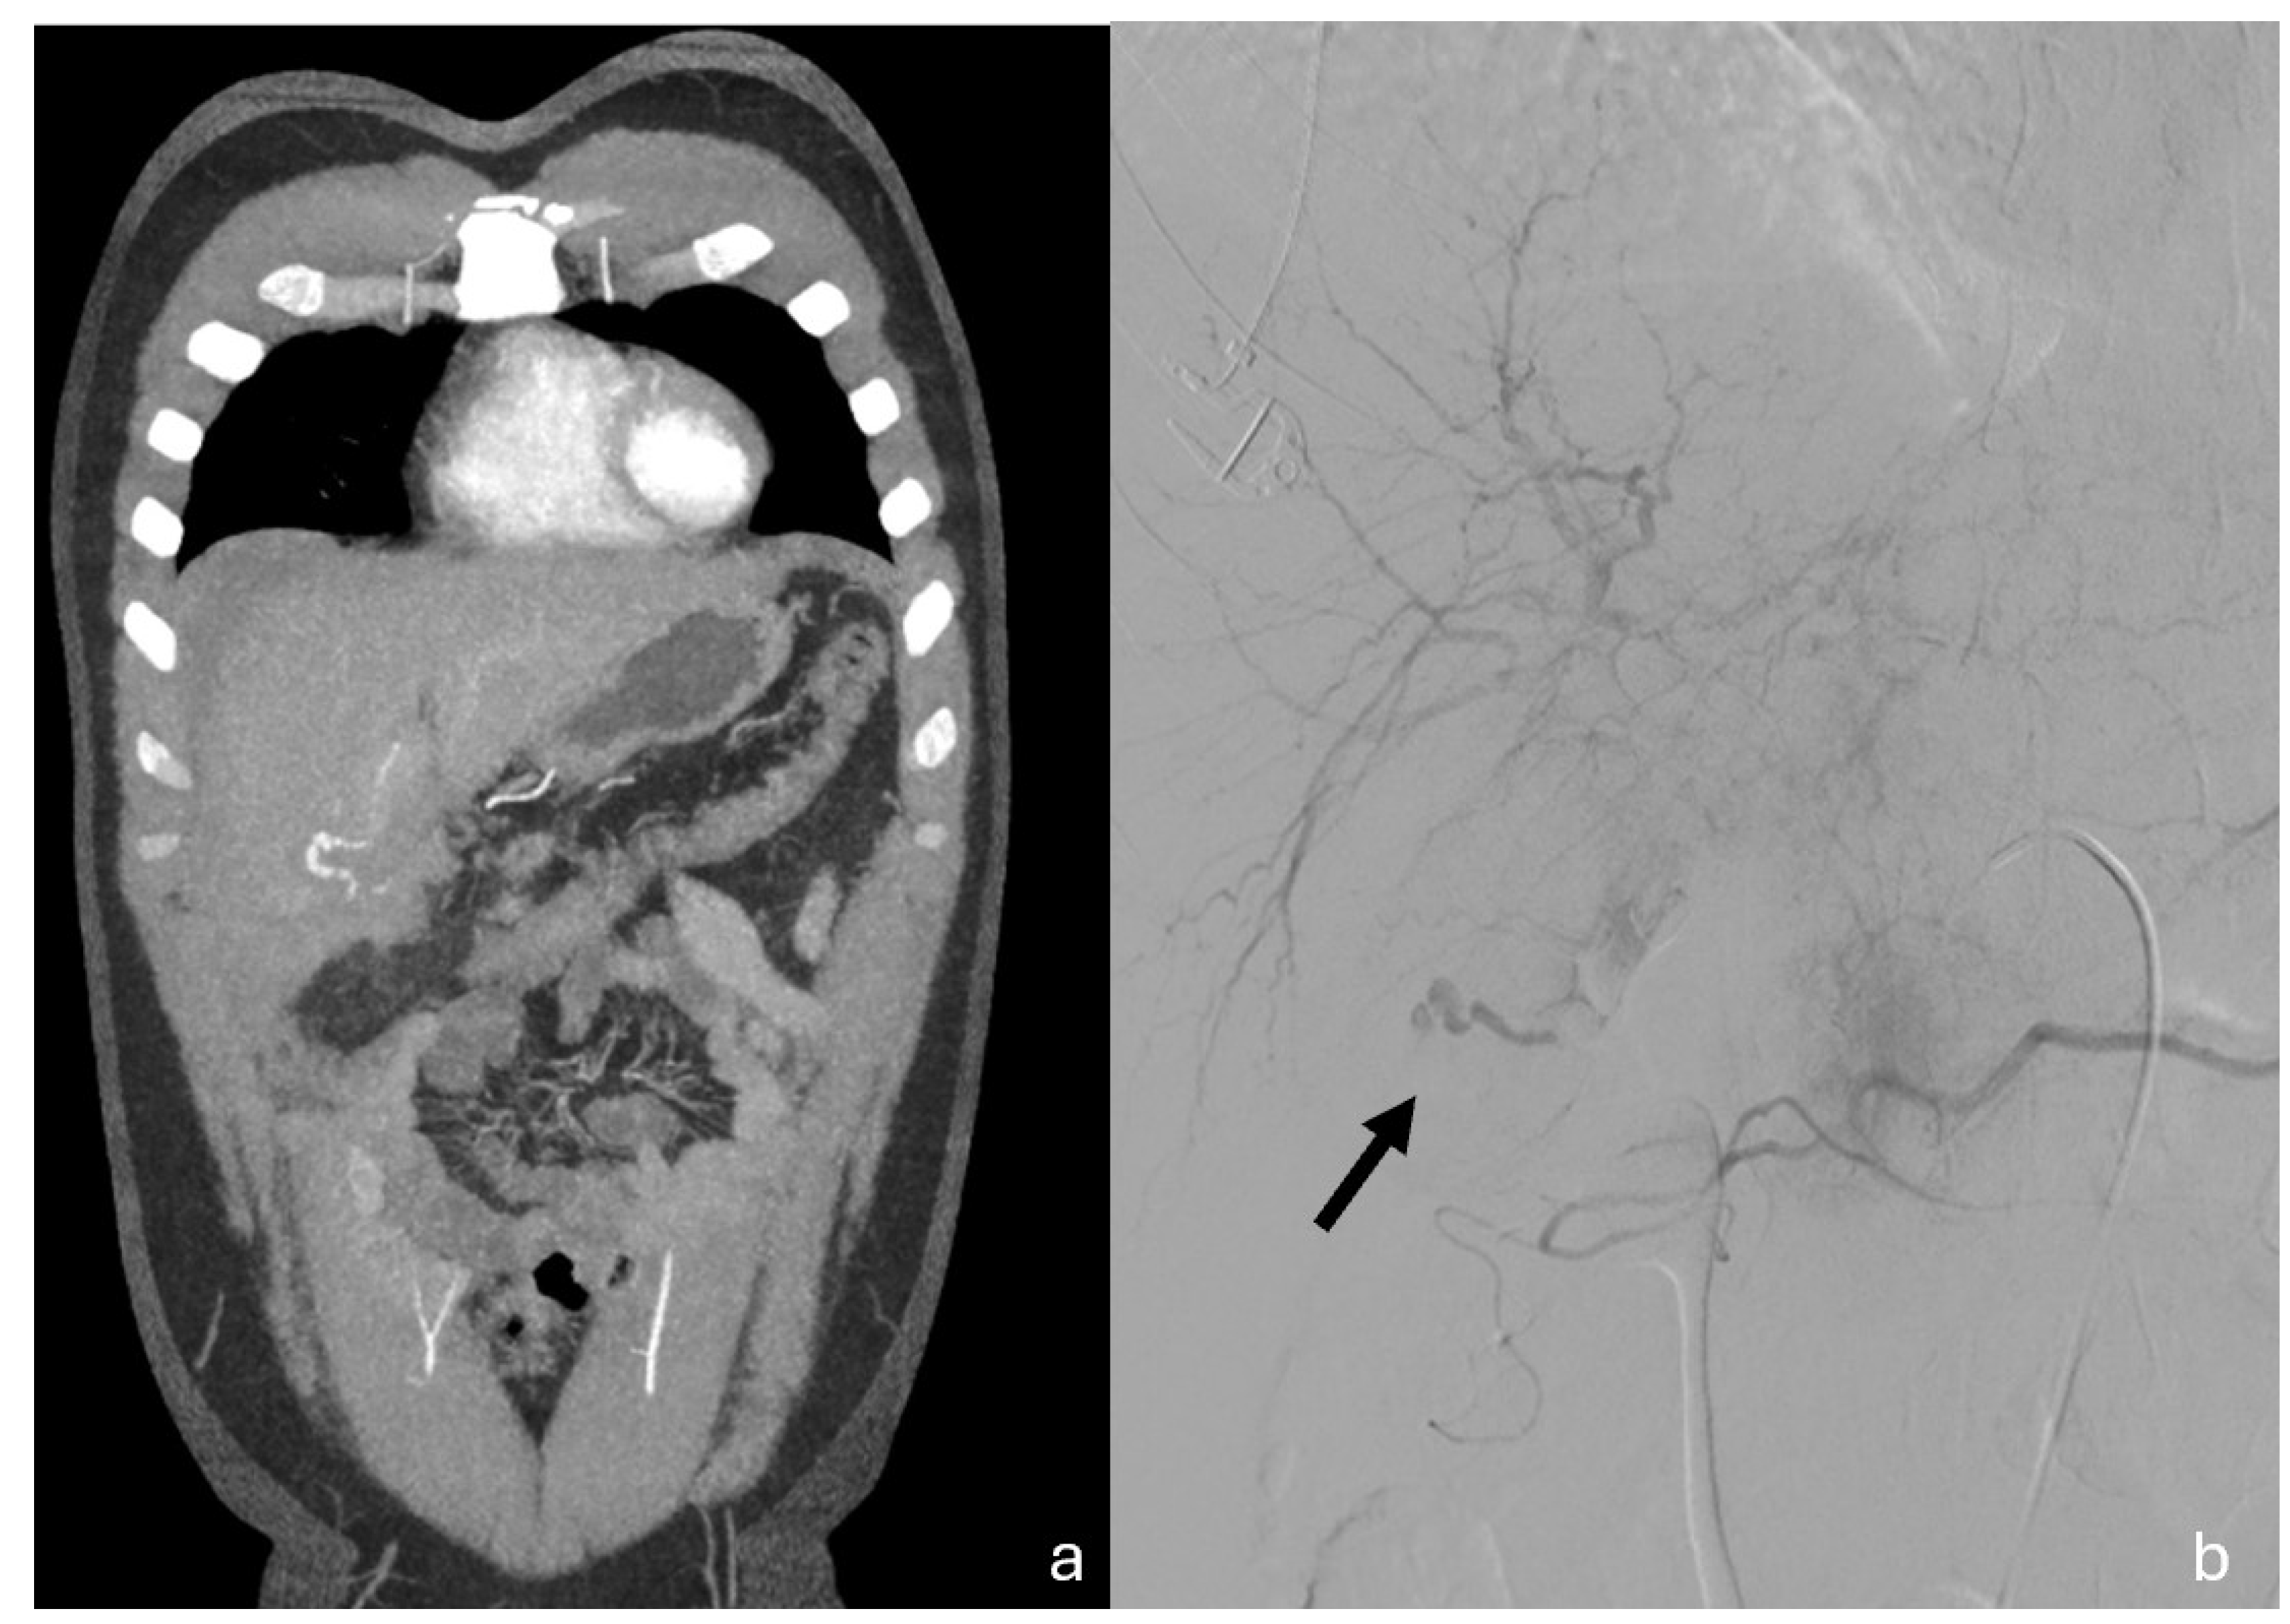

Figure 4.

Coronal MPR CT images (a) and Angiography (b) both showing cystic artery conspicuous bleeding. (b)Digital subtraction angiography demonstrates the entity of the bleeding; black arrow pointing towards the cystic artery and the extravasation. The patient underwent TAE successfully with super selective embolization of the anterior branch of the cystic artery (spiral and embolic material). Hepatic laceration was treated conservatively. Postoperatively, the patient was stable and with good recovery and discharged on 14th day.

Figure 8.

MPR coronal (a) and sagittal (b) clearly demonstrate cystic branch pseudoaneurysm bleeding.